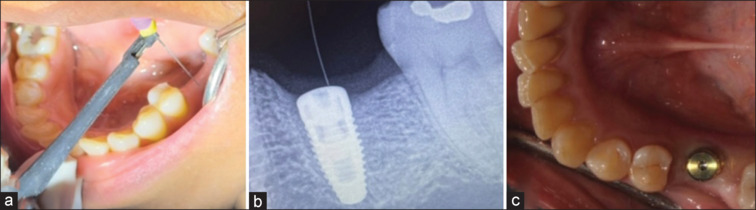

Materials and methods: The study employed apex locator (Woodpecker Woodpex III Gold 5th generation) in conjunction with a K-file (Mani k-file #10, 21 mm) for detecting the implant location. The accuracy of the novel technique was determined based on the values measured on the apex locator, with positive values indicating soft-tissue response and negative values indicating the cover screw (metal). The accuracy was cross-verified using radiovisiography (RVG). The clinician-based scoring was also done, considering RVG evaluation, amount of incision given, and ease of the procedure. The time required to locate the cover screw was recorded using a timer for both the novel technique and the conventional method.

Results: The results revealed a significant difference in terms of incision given, ease of treatment, and time taken for the procedure (P < 0.05), while the accuracy of the novel technique was not disturbed (P > 0.05).

Conclusion: Based on the findings of this in vivo study, the use of an apex locator as an alternative to conventional methods for detecting cover screw location at the second stage of recovery is recommended. The novel technique demonstrated faster uncovering of implants without posing any risks to the surrounding tissues or implants.